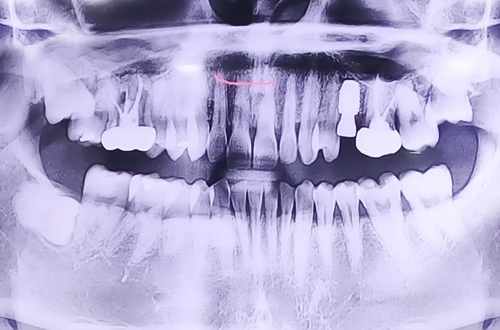

AFTER

X-ray 상에서는 치아에 큰 이상이 없어 보였지만 치아를 자세히 검사해 보니 왼쪽 위 어금니가 반으로 쪼개진 상태로 발치 이후 즉시 임플란트 치료를 진행하였고 뼈가 비어있는 부분들은 임플란트 주변 뼈이식을 진행해 드리면서 마무리해드렸습니다.

현재는 임플란트 위로 치아머리를 만들기 위한 부품을 끼워 놓은 상태이며 추후 임플란트가 단단히 자리 잡고 난 뒤 보철이 완성되면 다음 진료일지로 찾아뵙도록 하겠습니다! ^^